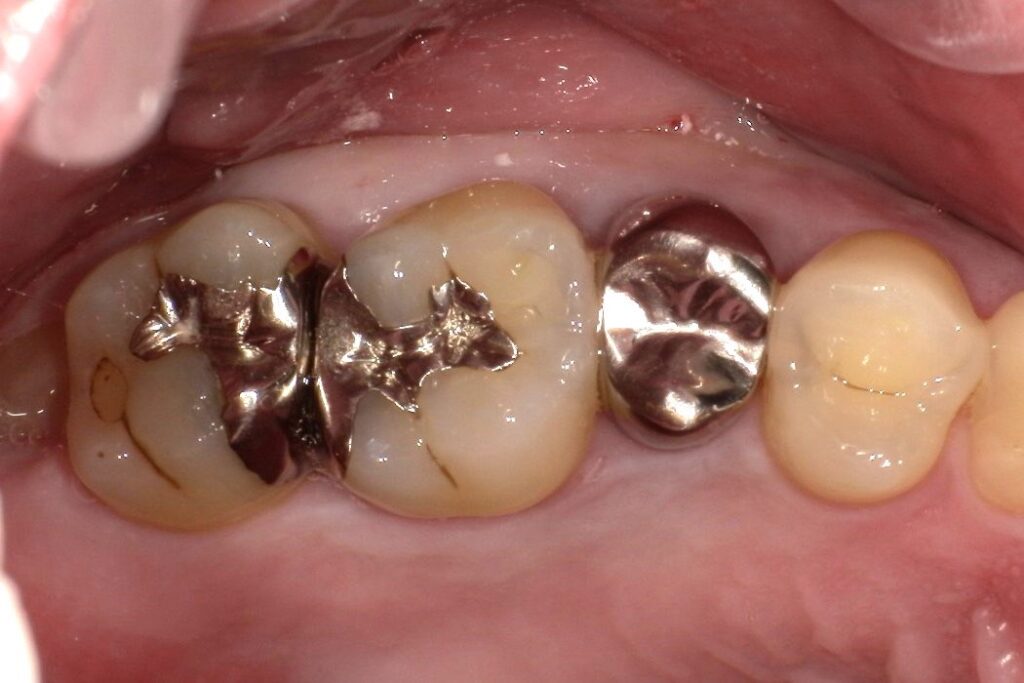

Case.01

治療前

治療後

| 主訴 | 虫歯を治したい。白く強度のあるものにしたい。 |

| 治療期間 | 1か月(3回) |

| 治療費 | 1本 ¥80,000+税 |

| 治療内容 | 右上4,5,6番目の虫歯を除去し、セラミックインレーを装着しました。 |

| 治療のリスク | 神経を温存しています。一時的に知覚過敏の症状が出ることがあります。また、咬合の強い方の場合、材料の破損の恐れがあり、夜間のマウスピースの装着をお勧めしております。 |